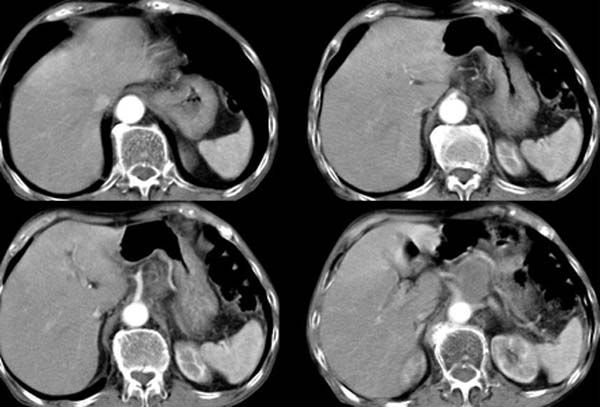

以下是引用zsl6918在2008-4-12 22:27:00的发言:[br]肝内未见异常密度灶,脾脏大小如常,腹主动脉旁可见一肿大淋巴结影,密度均匀,未见明显坏死表现。腹腔干被包绕,但未见明显侵犯,胃腔充盈尚可,未见明显占位表现。胰腺显示良好,略示前方移位。考虑腹膜后淋巴瘤可能性大。依据,转移瘤多有坏死表现,且有恶性肿瘤病史。第二,淋巴瘤未经治疗很少出现坏死表现,此点符合。第三,腹膜后其他肿瘤已经发现一般较大,本病例结节大小符合肿大淋巴结的表现。故首先考虑淋巴瘤。建议临床进一步检查其他部位的情况,另外结合实验室检查,注意病人有无贫血及低热表现。